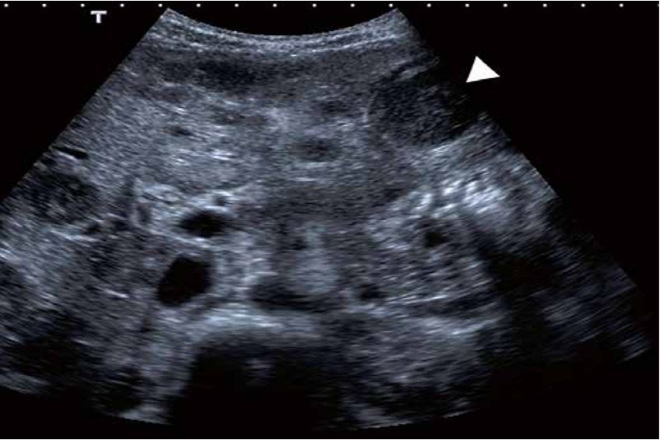

Lo fundamental es discernir la posible etiología benigna o maligna de la lesión. La presencia de una lesión focal hepática constituye un reto en la evaluación clínica y métodos diagnósticos no invasivos como el ultrasonido abdominal, permite detectarlos y caracterizarlos. Aunque la sensibilidad para detectar una de este tipo de lesiones hepáticas con ultrasonido varía en función del tamaño, la localización o la patología hepática de base, este método proporciona datos semiológicos sugestivos de benignidad o malignidad de la lesión.

La lesión focal hepática fue identificada por ecografía en el 100% de los pacientes. En el 56% fue un hallazgo incidental, mientras que el 43% fue sugerido por las manifestaciones clínicas y la elevación en diferentes grados de las alaninotransferasas.

Se concluye que las lesiones focales hepáticas pueden presentarse a cualquier edad, son asintomáticas en su mayoría y el ultrasonido abdominal es el método de elección para el diagnóstico y seguimiento de estas lesiones, mientras el origen de las mismas, guía la conducta terapéutica.